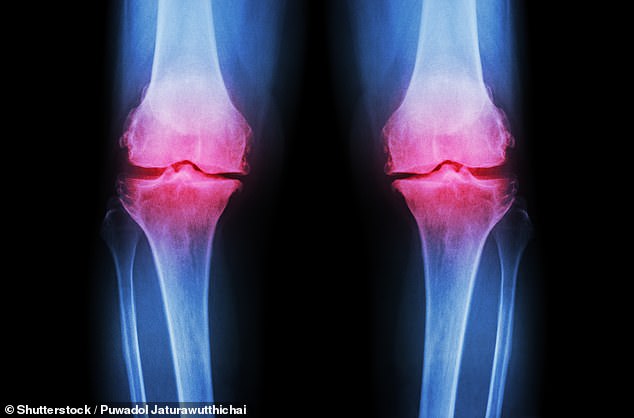

The decline in lipid metabolism during the 40s is particularly concerning. As people age, their bodies become less efficient at processing fats and sugars, increasing the risk of high cholesterol. This can lead to plaque buildup in arteries, straining the heart and raising blood pressure. Foods high in saturated fats—such as processed meats, dairy, and fried goods—exacerbate this issue. At the same time, bone density begins to decline, raising the risk of osteopenia, the early stage of bone thinning that can progress to osteoporosis. The Royal Osteoporosis Society (ROS) warns that one in two women and one in five men over 50 may suffer a fracture due to osteoporosis, calling it an 'escalating public health crisis.'

Prevention is key, experts say. Professor Hamish Simpson of Queen Mary University of London highlights that osteopenia is often 'a silent condition,' with symptoms only appearing after a fracture. 'Eating well, reducing alcohol intake, and increasing exercise can all reduce the risk of falls and fractures in later life,' says Dr. Richie Abel of Imperial College London. He recommends a calcium-rich diet from food sources like dairy rather than supplements, alongside vitamin D supplements. For bones, Simpson emphasizes the importance of 'loading exercises' such as jumping or skipping, which stimulate bone growth by creating small shocks to the skeleton.